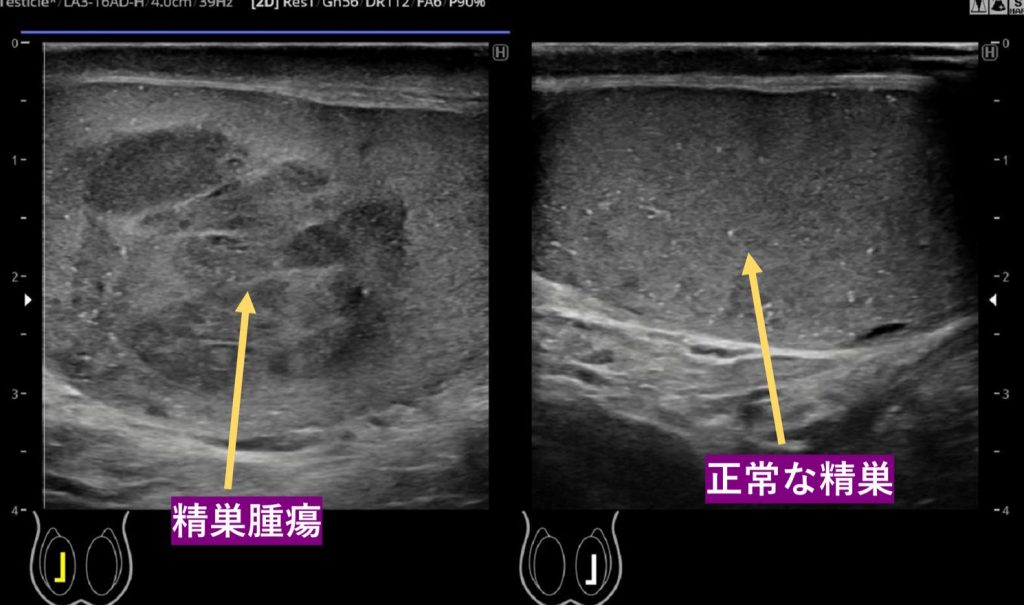

ステージ2の精巣がんとは何ですか?

ステージ 2 の精巣がんは、精巣のどこにでも発生します。陰嚢や陰嚢などの他の構造に転移している可能性があります。

ステージ 2 の精巣がんは、少なくとも 1 つの近くのリンパ節に転移していますが、肺や脳などの離れた体の部分には転移していません。